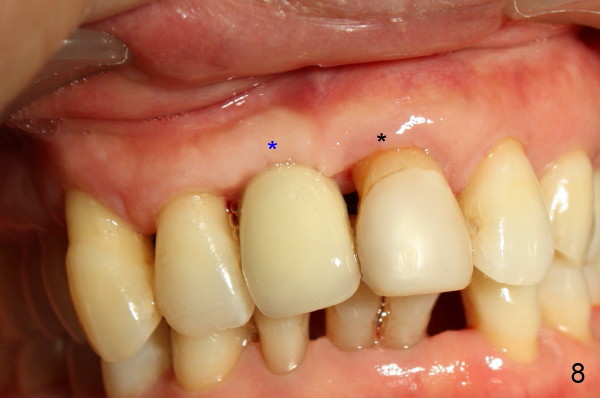

Fig.7 shows the gingiva around the crown (to be cemented) with healing incision #2. Five months after crown cementation, the gingiva looks healthy (Fig.8 blue *, as compared to that of the neighboring tooth, black *). Return to original article